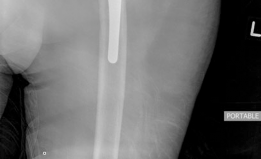

For Paprosky Type II and IIIA defects, where the metaphyseal bone is absent but the diaphyseal isthmus is intact, modular fluted tapered titanium stems are the implant of choice. These stems feature a distally fluted geometry that engages the diaphyseal cortex, providing rotational stability, and a 2-to-3-degree taper that provides axial stability via a wedge effect.

The diaphysis is sequentially reamed until cortical chatter is achieved, indicating engagement of the dense cortical bone. The proximal body is then selected independently to restore leg length, offset, and version. This modularity is crucial for optimizing hip biomechanics independent of distal diaphyseal fixation. It is imperative that the stem achieves a minimum of 4 to 6 centimeters of scratch fit distal to any defect or the distal extent of an ETO to prevent subsidence.

For Paprosky Type IIIB defects, the isthmus is compromised, making diaphyseal engagement unpredictable. In these instances, longer, curved modular stems that bypass the deficient isthmus and engage the distal femoral metaphysis or even the epiphyseal scar may be required.

- Richards et al. (Modular Tapered Stems): Biomechanical and clinical studies validating the use of modular fluted tapered titanium stems. The literature confirms that achieving a minimum of 4 cm of diaphyseal scratch fit is critical for preventing subsidence and achieving long-term survivorship in Paprosky IIIA and IIIB femoral defects.